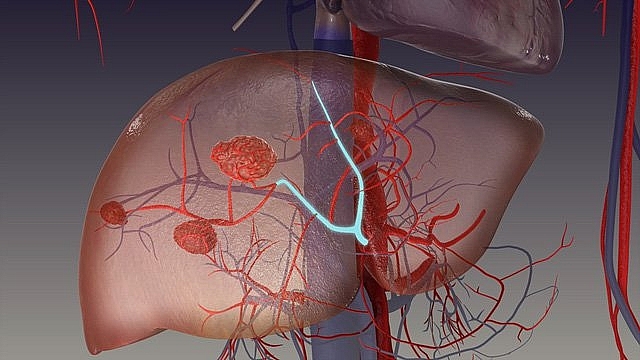

Theo bác sĩ Hoàng Thị Thu Hà, Trung tâm Y tế TX Từ Sơn, u máu trong gan thường được gọi nôm na là u máu trong gan hay u máu gan, đây là một khối u lành tính hay gặp nhất của gan. U máu không chỉ xuất hiện ở gan mà có thể xuất hiện ở bất cứ vị trí nào của cơ thể. U máu trong gan không có triệu chứng lâm sàng, nhưng những u lớn có thể gây đau hạ sườn phải, gan to hoặc xuất hiện khối u ở ổ bụng. Biến chứng có thể gặp khi bị u máu trong gan có thể là chảy máu trong khối u hoặc khối u vỡ chảy máu trong ổ bụng.

Theo bác sĩ Hà, bệnh nhân khi phát hiện u máu trong gan thường có tâm trạng lo lắng và tìm cách điều trị. Hầu hết u máu trong gan không cần điều trị, đây là khối lành tính hiếm khi gây ác tính. Cho tới nay chưa có một loại thuốc nào có tác dụng làm mất hoặc giảm kích thước của khối u. Người ta chỉ điều trị khi khối u lớn và gây các triệu chứng như khi có đau nhiều bằng nút mạch gan hoặc phẫu thuật cắt một phần của gan.

Nghiên cứu cho rằng hormon sinh dục nữ (oestrogen) có thể làm cho khối u máu lớn nhanh do vậy khi phát hiện có u máu trong gan không nên dùng các thuốc có chứa oestrogen kéo dài, chẳng hạn như dùng thuốc tránh thai. Đối với những người có u máu trong gan cần kiểm tra định kì bằng siêu âm 6 tháng 1 lần để theo dõi kích thước của u máu. Đối với người có khối u máu lớn cần thận trọng để tránh va đập vào vùng mạng sườn phải gây vỡ khối u. Khi có biểu hiệu đau đớn kéo dài thì bệnh nhân cần trực tiếp đến bệnh viện theo dõi.